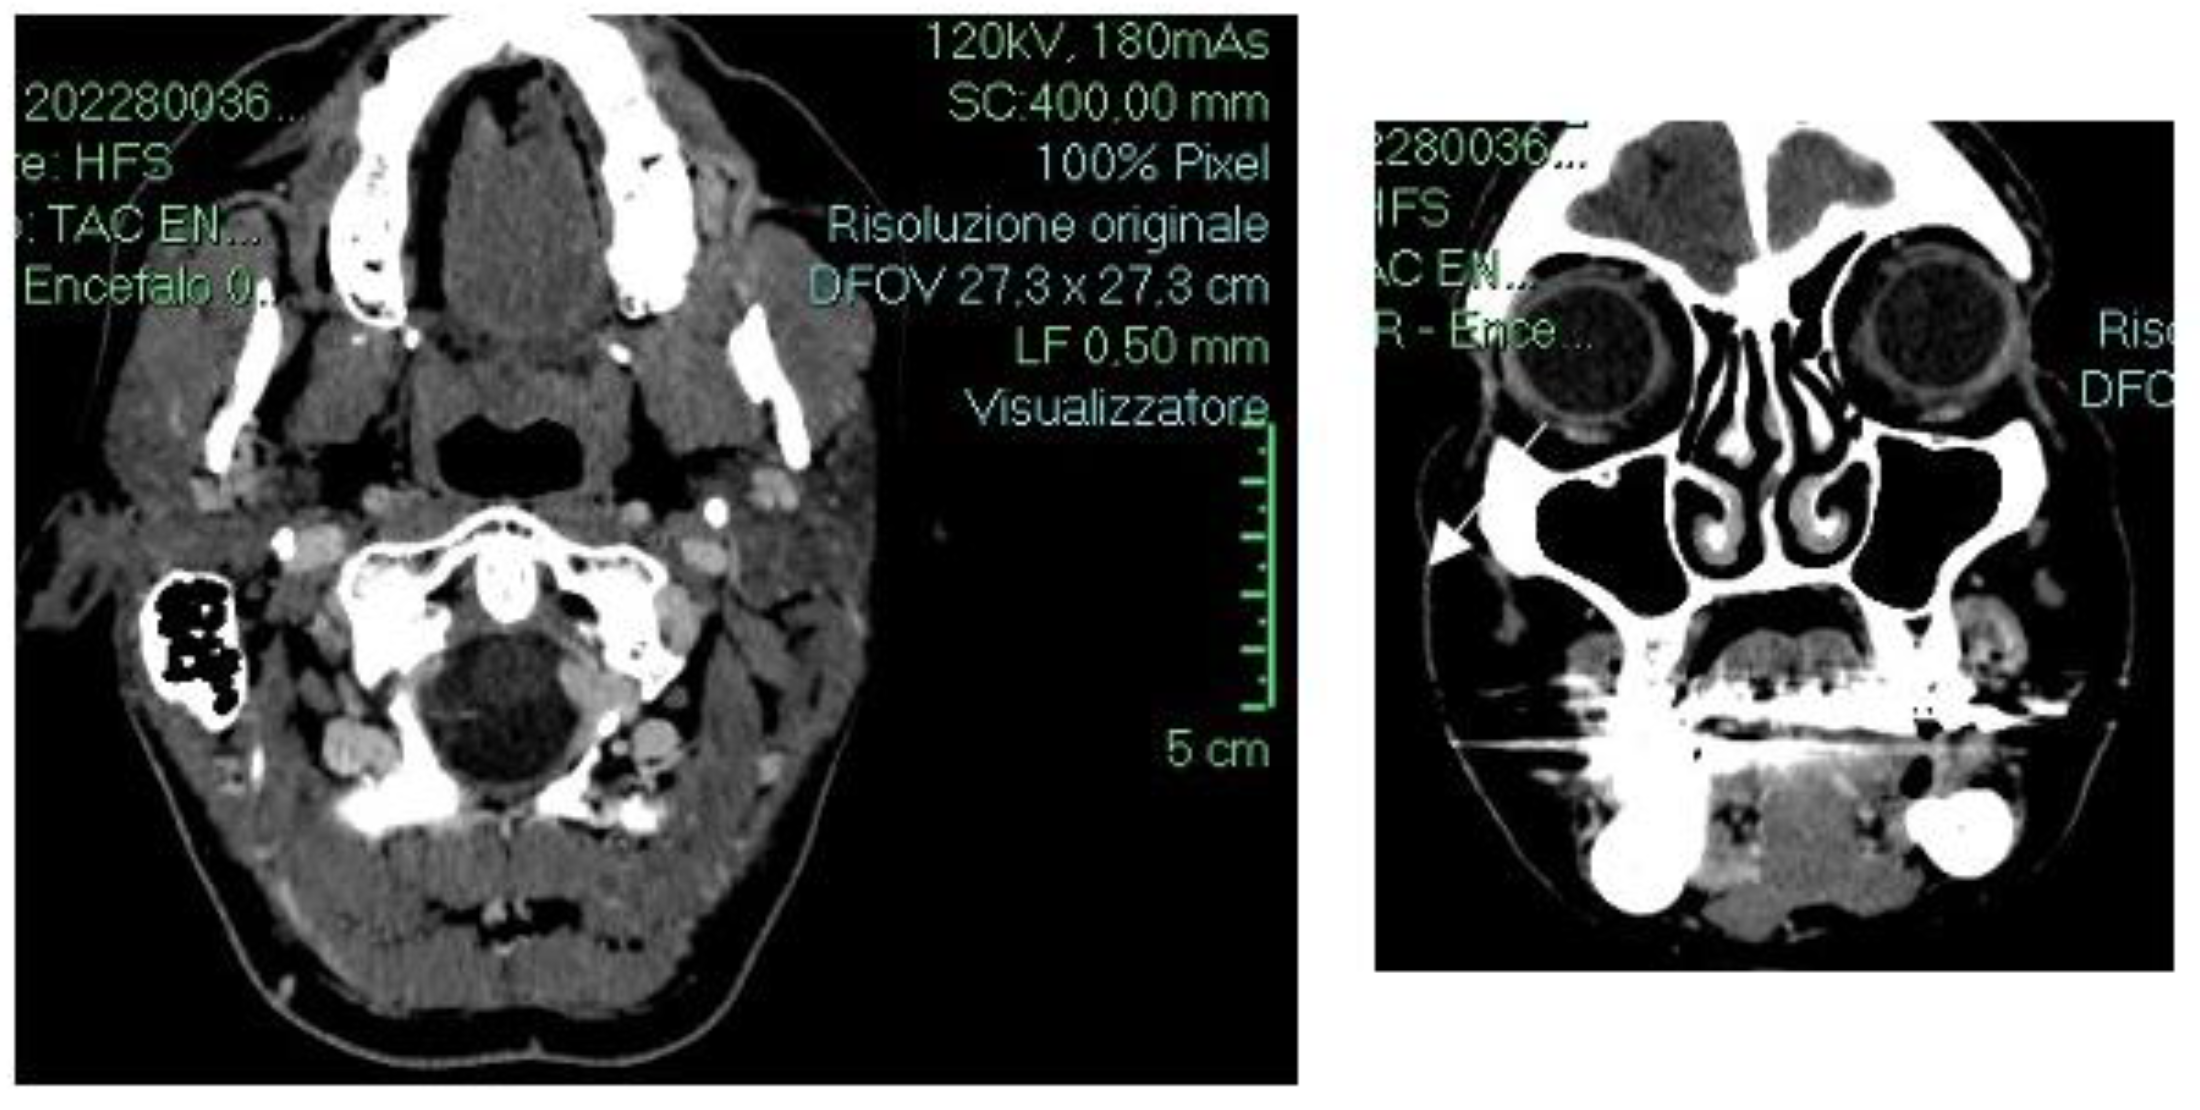

Based on the clinical features, microscopic findings, and histopathological examination, a diagnosis of angiosarcoma of the oral cavity was performed. Total body computed tomography (TB CT) imaging revealed a small soft tissue density lesion involving the upper left lateral alveolar mucosa. The lesion appeared as an inhomogeneous enhanced 2 cm ovoid mass with polycyclic borders (indicated by the white arrow). There was no evidence of generalized cervical lymph node enlargement or other localizations of angiosarcoma (Figure 3).

Figure 3.

Axial and coronal CT images showing the Angiosarcoma.